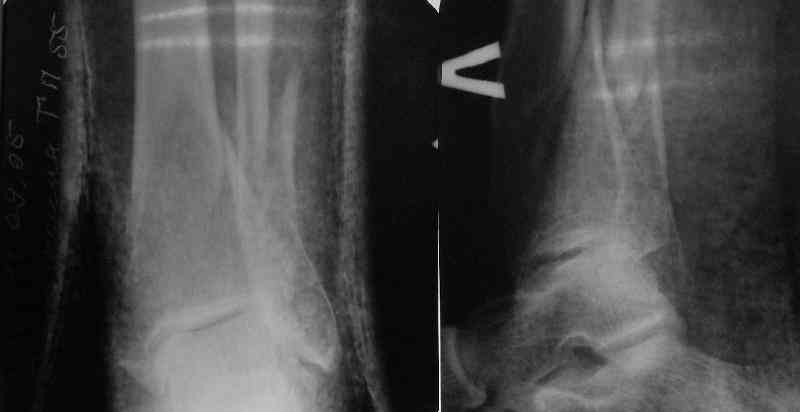

There are some more tricks which allow not to plate the fibula and provide good alignment and stability. A small wire distractor can provide alignment and restore length of both tibia and

fibula. Angular stability of the tibia is provided by insertion of more than two conventional medial-lateral locking screws. To maintain the position of the fibula perQ insertion of a single position screw often could be enough. I bet the articles didn't analyze the options.

A typical case is attached, also an image with intra-op reduction obtained by a small wire distractor, in the moment of insertion a Poller wire in AP direction. Fixation by a SIGN nail. Despite the fibula was not fixed healing was obtained with the unchanged alignment.